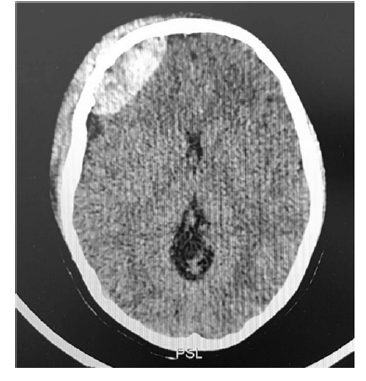

Um menino de dez anos de idade, vítima de trauma cranioencefálico, foi levado ao hospital pelo resgate após queda do telhado de uma altura de 5 m. Deu entrada na emergência com Glasgow de 13, evoluindo com crise convulsiva, tratada adequadamente com medicação. Foi realizada, ainda, uma tomografia de crânio que apresentou a imagem seguinte.

Com base nesse caso hipotético, assinale a alternativa correta.